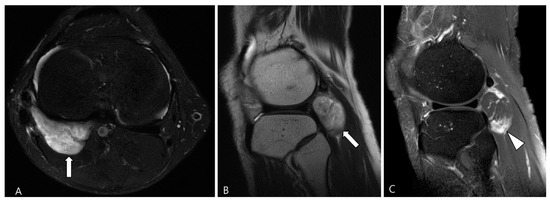

2.3. Morphological Findings for D-TSGCT

2.4. Relationship to Adjacent Structures of D-TSGCT